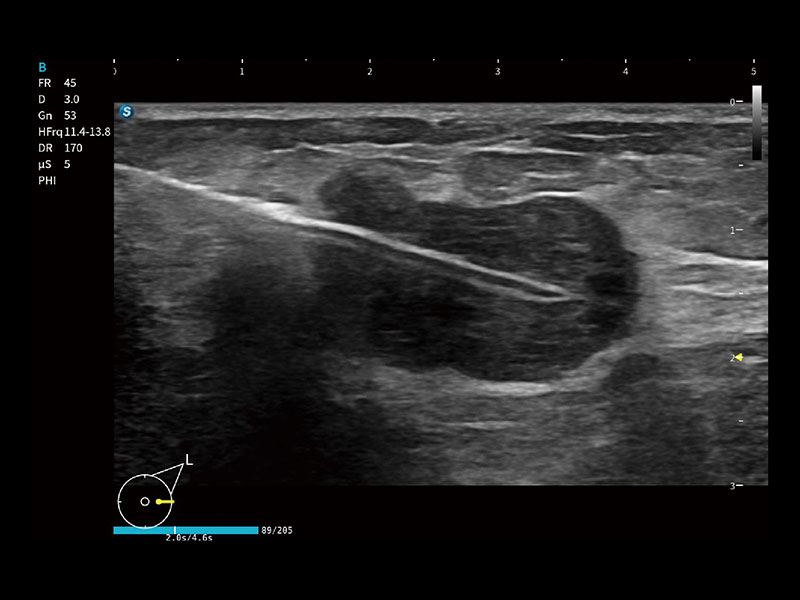

作为开立医疗全新打造的高端床旁笔记本超声,E11不仅具备卓越的图像质量,同时搭载全面高效的自动测量工具,助力医生实现更快速、更精准的床旁诊断。

E11搭载了丰富的自动化测量工具,以及专为POC科室定制的高级功能;同时配备了为急诊医师量身打造的 SonoFast急重症超声流程,以帮助临床医生最大限度的提升工作效率